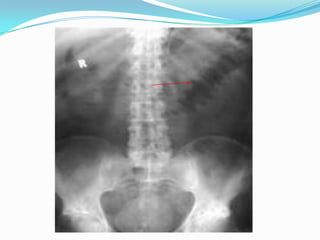

Plain radiograph

 In severe disease, the luminal margin of the colon becomes

edematous and irregular.

 Thickening of the colonic wall often is apparent on a plain film

 Plain films also are useful for detecting the presence of fecal

material.

 The presence of marked colonic dilatation suggests fulminant

colitis or toxic megacolon.